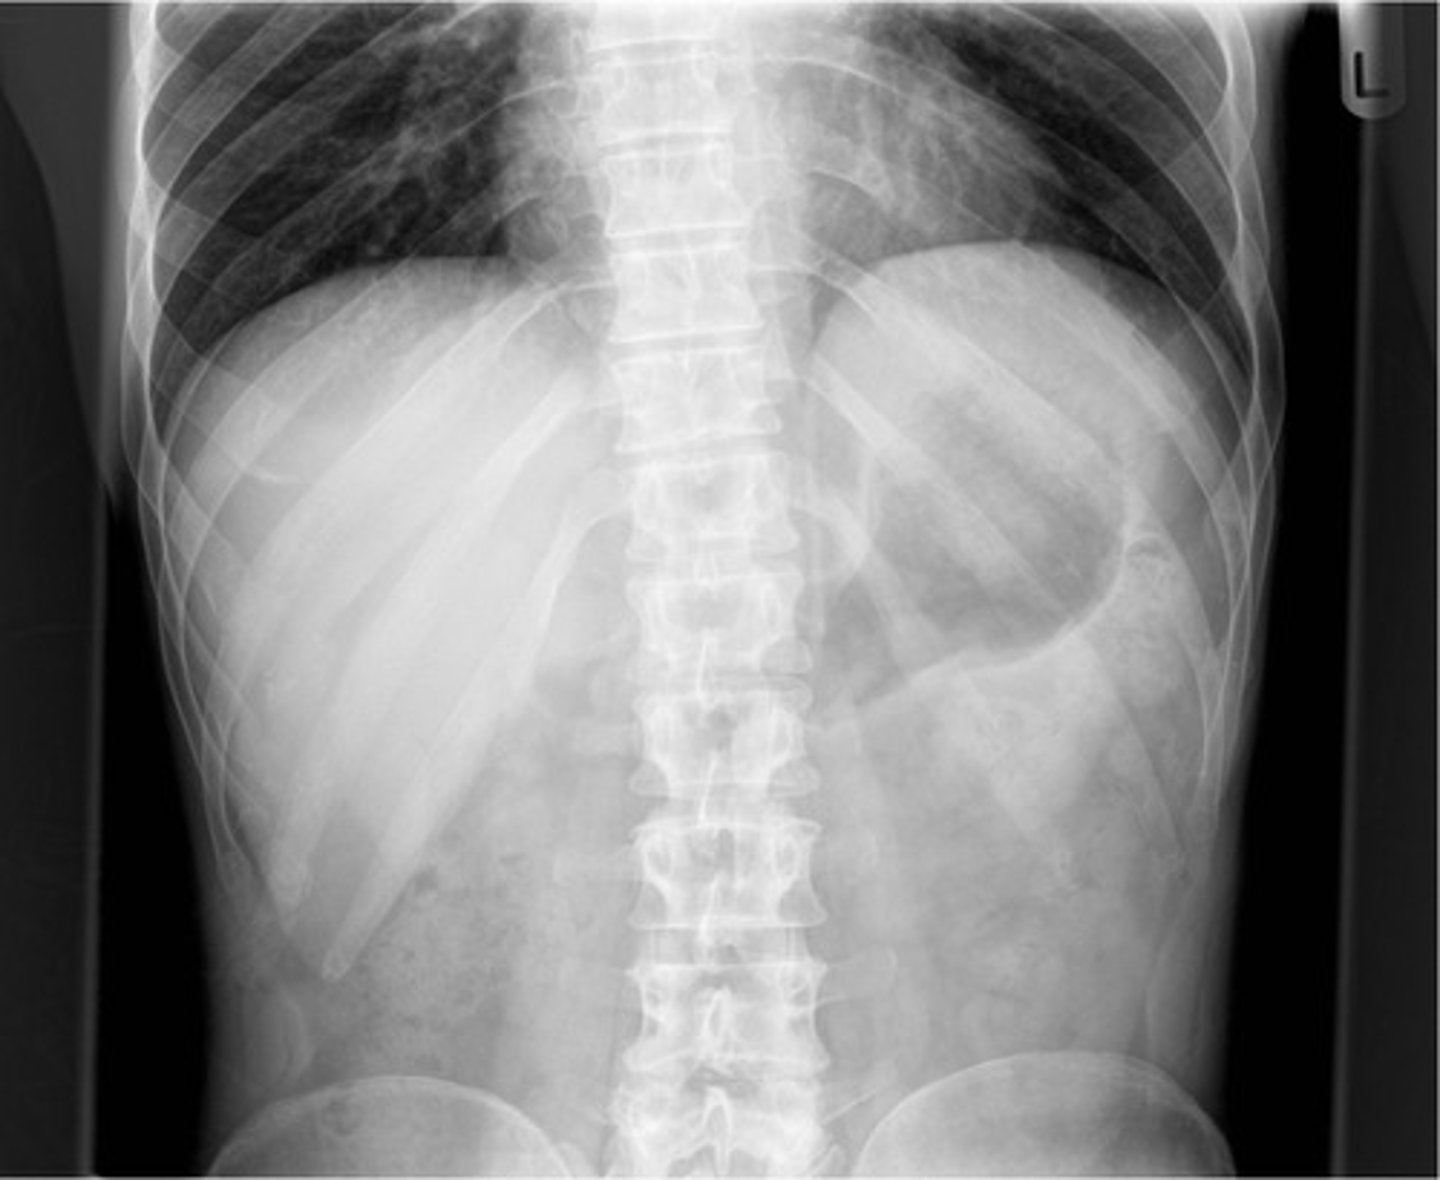

Normal supine AXR

Normal AXR (and normal size liver)

Normal AXR (and normal organs)

Normal AXR (and normal structures)